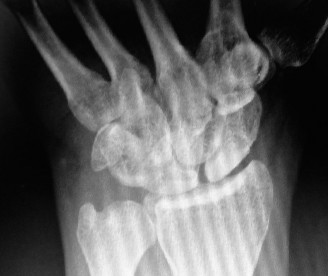

Radiographic evaluation requires specific, non-standard views. A standard PA and lateral of the wrist will often obscure the pisiform due to bony overlap. Therefore, a 30-degree supinated lateral view or a carpal tunnel view is essential to profile the pisiform and evaluate the pisotriquetral joint space. In cases of delayed union or subtle comminution, a fine-cut non-contrast Computed Tomography (CT) scan provides invaluable three-dimensional mapping. For the elderly patient presenting with progressive, non-traumatic base of thumb pain, standard radiographs must include a Robert's view (a true AP of the first CMC joint) and stress views to evaluate the degree of radial subluxation. The image above clearly demonstrates advanced 1st CMC arthritis, characterized by complete loss of joint space, subchondral sclerosis, and osteophyte formation, confirming the diagnosis.